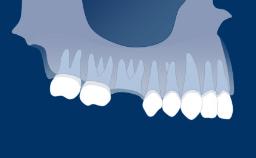

Tooth loss is one of the most common disabilities affecting mankind, and is a consequence of dental diseases, tumors of the orofacial region and trauma. Missing teeth may also occur because of agenesis.

The extent of missing teeth can vary, from single teeth in the anterior region of the jaws, single teeth in posterior segments, extended edentulous spaces and edentulism. This may result in functional, esthetic and phonetic impairment for the individual concerned.